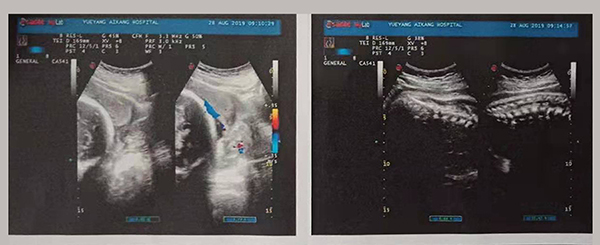

近日,岳阳爱康医院产科团队成功抢救了一名完全性前置胎盘的产妇。完全性前置胎盘是妊娠期的严重并发症,是分娩期子宫切除的一个重大高危因素之一,是引起孕产妇死亡和围生儿死亡的重要原因之一。

2019年8月24日,易女士出现阴道流血,在岳阳县人民医院住院,住院期间予以安治、止血,于26日出院。28日早晨6点再次出现阴道流血,量多、颜色鲜红、三片卫生巾均浸透,遂来岳阳爱康医院产科。

术中,摆在产科团队面前的第一个严峻考验出现了,整个子宫下段前壁膨隆血管怒张!迅速设计子宫切口,取出胎儿,面临又一严峻的考验,胎盘大面积植入整个子宫下段前后壁,迅速行双侧子宫动脉下行支结扎,迅速人工剥离胎盘以及卵圆钳钳夹剩余胎盘组织,植入的胎盘处理干净后子宫下段前后壁多处肌层缺损伴有大量活动性出血,迅速行子宫下段整形修复缝合止血……不得不说产妇是幸运的,妇产科、手术麻醉科等多科通力合作,经过约2小时的手术及抢救止血,术中共计出血1500ml,输悬浮红细胞4个单位,终于保得母女平安,并完美的保留了子宫。易女士术后恢复良好,对妇产科的精湛技术赞不绝口!